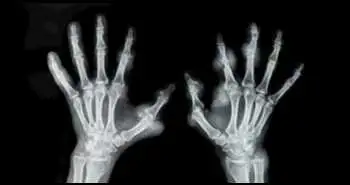

Ефективність терапії сарілумабом протягом 5 років у пацієнтів з ревматоїдним артритом, які не піддаються лікуванню інгібіторами ФНП

В ході дослідження, проведеного Roy Fleischmann і співавт., встановлено, що застосування сарілумаба (людського моноклонального антитіла) у пацієнтів з РА, які не піддаються лікуванню інгібіторами ФНП, забезпечує досягнення стійкої ефективності протягом 5 років.

Пацієнти з РА, які отримували плацебо або сарілумаб в дозі 150 мг або 200 мг 1 раз на 2 тижні в поєднанні з терапією стандартними синтетичними базисними протиревматичними препаратами (ссБПРП) в дослідженні TARGET тривалістю 24 тижні, могли бути включені в довгострокове відкрите додаткове дослідження (ВДД) для отримання сарілумаба в дозі 200 мг кожні 14 днів в комбінації з терапією ссБПРП. Зниження дози в ВДД до 150 мг 1 раз на 2 тижні допускалося за рішенням дослідників або з міркувань безпеки згідно з протоколом.

В ВДД взяли участь 454 з 546 пацієнтів (83%), які отримували сарілумаб. Загальний період дослідження склав 1654,8 пацієнто-років, при цьому 268 пацієнтів (51%) отримували терапію протягом більше 4 років. Частота розвитку небажаних явищ (НЯ), частота припинення лікування через розвиток НЯ і частота розвитку інфекції на 100 пацієнтів-років склали 160,4, 8,1 і 57,8 відповідно. Найбільш частим НЯ була нейтропенія. У 74 пацієнтів (14,2%) загальна кількість нейтрофілів становила <1000 клітин / мм3, і у 48 пацієнтів, які отримували терапію сарілумабом, кількість нейтрофілів вдалося нормалізувати. За результатами подальшого спостереження протягом 5 років була доведена стійка клінічна ефективність терапії. Ефективність терапії у пацієнтів, які продовжували приймати сарілумаб в дозі 200 мг або знизили дозу до 150 мг, була порівнянна.